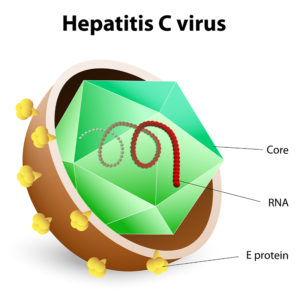

Direct-acting antivirals are medications that act to stop the hepatitis C virus replicating. The duration of treatment with DAA medicines varies in length from 8 to 24 weeks. These drugs are taken orally.